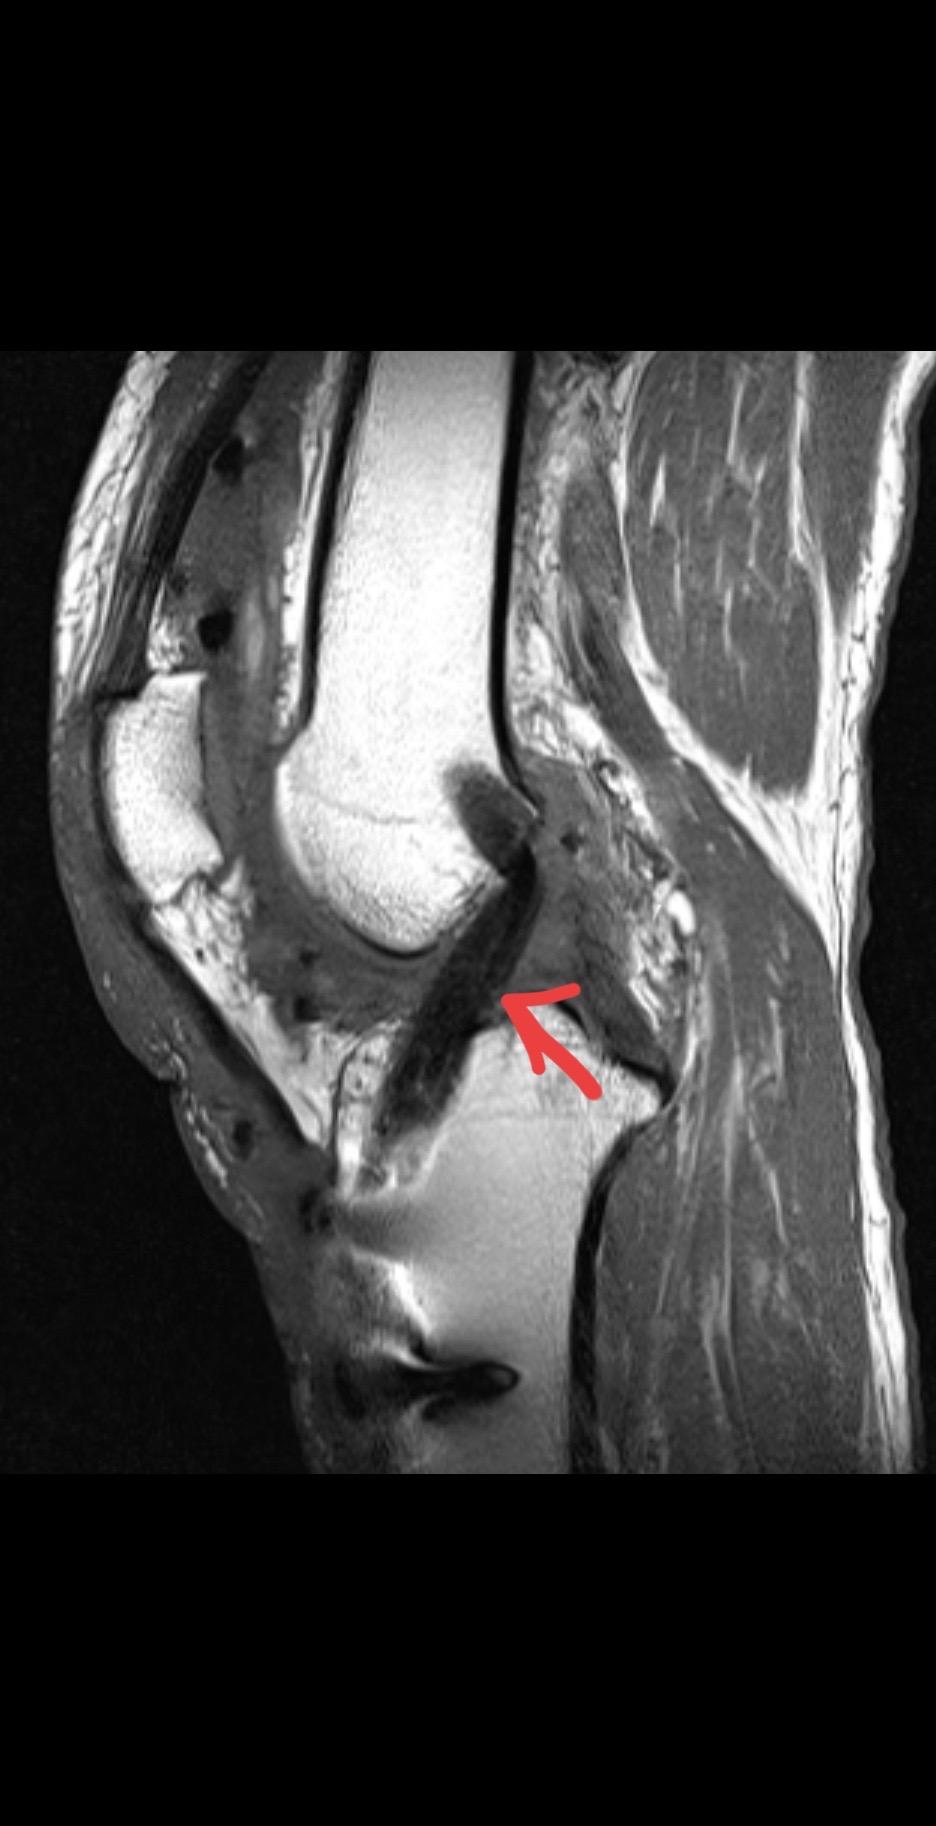

前交叉韧带重建术后影像评估。